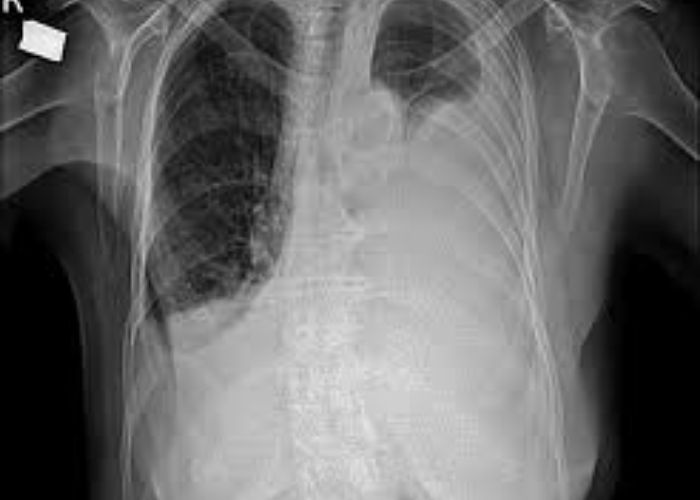

AMPİYEM

Plevral yaprakları arasında sıvı birikmesi ve sıvının enfekte olması , koyulaşması ve kötü kokulu hal almasına Ampiyem denir.  Ampiyem enfeksiyonlara sekonder olabileceği gibi göğüs travması sonra ve göğüs içi yabancı cisim sonrasında da gelişebilir.

Ampiyem tanısı konulur konulmaz erken müdahale yapılıp tedaviye hemen başlanmalıdır. Son yapılan çalışmalar doğrultusunda ilk olarak VATS veya RATS önerilir (Dekortikasyon )ve toraks tüpü yerleştirilip, antibiyotik tedavisi başlanıp hasta takibe alınmalıdır.